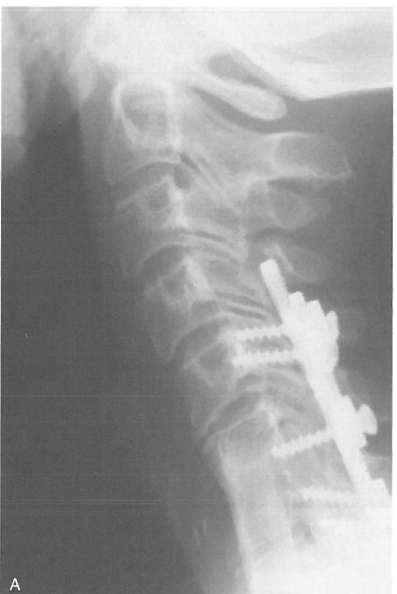

海外医疗机构爱诺美康介绍,当在C7和T1节段进行椎体切除时,不能简单地通过侧位像评估植人物的位置(图,A)。通过斜位像可以相对容易地辨别外形(图,B)。如对C7-T1区域进行充分的评估,就需要进行比X线平片优越的CT检查。CT可以正确显示横突和肋骨头周围的解剖结构,还可以提供矢状位图像,以便于术者决定植入物和器械的正确位置。如果进行CT检查,通过轴位和矢状位检查可以轻易显示植骨和内固定器械的位置(图,C和D)。